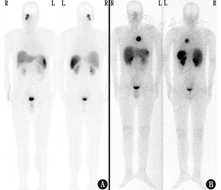

患者女,41岁,主诉腰部不适1个月,无发热、头痛、恶心、呕吐、腹痛、腹胀、腹泻、头晕、黑矇、大汗等症状。腹部CT发现右侧腹膜后软组织密度肿块;增强CT+三维重建图像示肿块大小约57 mm×40 mm,增强后明显强化,各期强化程度与血管相似,肿块局部与十二指肠分界欠清,下腔静脉呈受压性改变(图1)。实验室检查:24 h尿儿茶酚胺、血浆儿茶酚胺及其代谢产物(甲氧基肾上腺素、甲氧基去甲肾上腺素)、醛固酮(立位)、血管紧张素Ⅱ+肾素活性(立位)、神经元特异性烯醇化酶均正常。因临床拟鉴别副神经节瘤而行99Tcm-联肼尼克酰胺-酪氨酸3-奥曲肽(hydrazinonicotinamide-Tyr3-octreotide, HYNIC-TOC)生长抑素受体显像,平面显像可见右肾下方摄取轻度增高区,前位图像显示较清晰;SPECT/CT示病变位于下腔静脉前方,摄取轻度增高,与肝脏摄取程度接近(图2)。

综上所述,结合本例的CT表现,需主要鉴别副神经节瘤、Castleman病和炎性肌纤维母细胞瘤。就临床下一步诊治来说,手术切除是首选,但副神经节瘤术前需进行α-肾上腺素能阻滞剂准备(否则手术风险巨大),并且一般来说活组织检查为禁忌。所以本例鉴别诊断中最重要的问题是:是不是副神经节瘤?能不能除外副神经节瘤?副神经节瘤的典型症状是高血压伴阵发性头痛、大汗、心悸,本例主诉腰痛,为不支持点;副神经节瘤的实验室检查一般有24 h尿儿茶酚胺升高,本例为阴性,亦为不支持点;副神经节瘤在腹部一般位于腹膜后,强化明显,本例有相似特点;副神经节瘤属于神经内分泌肿瘤,表达生长抑素受体,生长抑素受体显像一般为阳性,本例在生长抑素受体显像中摄取轻度增高,可判定为弱阳性。

生长抑素受体显像对位于肾上腺外的副神经节瘤的诊断灵敏度很高(图3),文献报道68Ga标记生长抑素类似物显像对肾上腺外副神经节瘤诊断灵敏度可达100%[2,3],对肾上腺内副神经节瘤(嗜铬细胞瘤)诊断灵敏度<90%[2]。就诊断特异性而言,生长抑素受体显像阳性不等于就是神经内分泌肿瘤,很多类型的病变也可表达生长抑素受体2型,如脑膜瘤、肾癌、乳腺癌、淋巴瘤、肺癌、前列腺癌、头颈部肿瘤、肉瘤、甲状腺癌、星形细胞瘤、感染及炎性反应等[4,5],病例举例见图4。而关于本例需鉴别的其他2种疾病,近期有Castleman病生长抑素受体显像假阳性的报道[6,7],摄取程度与本例相似;虽然鲜见文献报道炎性肌纤维母细胞瘤的生长抑素受体显像情况,但炎性肌纤维母细胞瘤在病理上伴大量浆细胞和淋巴细胞浸润,而活化的淋巴细胞可有生长抑素受体高表达,理论上讲该病也有生长抑素受体显像假阳性的可能。